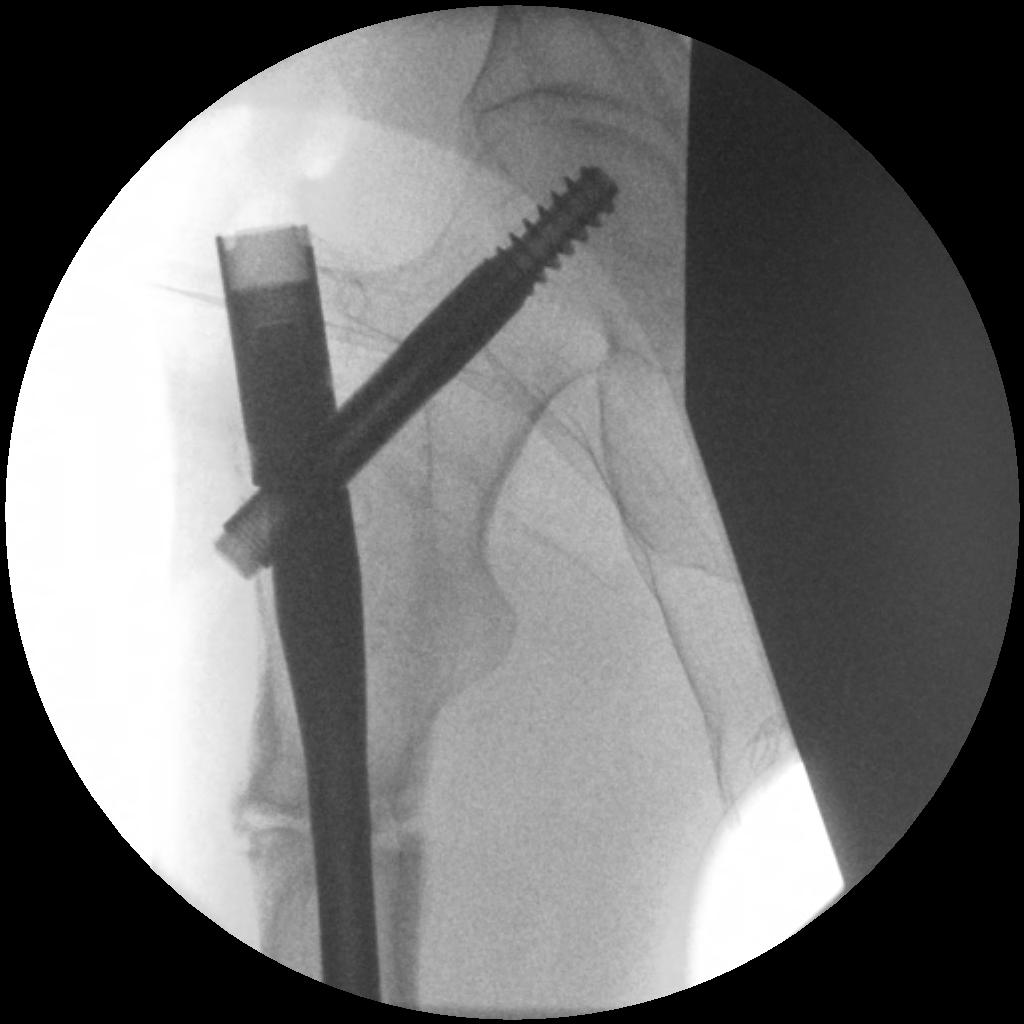

1. Cephalomedullary nail

- be careful of bowed femurs in Asian women

Nail aptypical 1Nail atypical 2

Femoral stress fractureFemoral Stress Fracture IMN

complete AFFNail AFF

- complete fractures: IMN nonunion rate 12.9%

- mean time to union 7 months post surgery